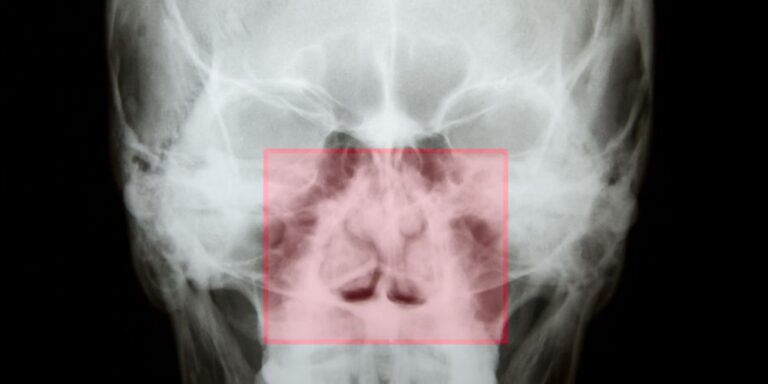

Η διάγνωση της σκολίωσης ρινικού διαφράγματος γίνεται γρήγορα, εύκολα και ανώδυνα από Ωτορινολαρυγγολόγο με την πρόσθια ρινοσκόπηση. Ο γιατρός, με ένα εργαλείο που λέγετε ρινοσκόπιο, κοιτάει μέσα από τα ρουθούνια και βλέπει άμεσα τα στραβά τμήματα του διαφράγματος καθώς και οποιαδήποτε άλλη διαταραχή. Για ακόμα πιο λεπτομερή εξέταση, είναι εφικτή η χρήση ενός εύκαμπτου ή άκαμπτου ενδοσκοπίου το οποίο δίνει την δυνατότητα βαθύτερης ανάλυσης και μεγέθυνσης της ρινικής κοιλότητας. Ένας πιο μαθηματικός και αντικειμενικός τρόπος ελέγχου είναι η ρινομανομετρία η οποία μετρά αξιόπιστα τον βαθμό απόφραξης των ρινικών κοιλοτήτων. Με τα πλέον σύγχρονα εργαλεία ρινομανομετρας μπορεί να διευκρινιστεί μέχρι και το ακριβές αίτιο της ρινικής δυσχέρειας. Η διάγνωση είναι απαραίτητο να γίνεται πριν την οποιαδήποτε χειρουργική παρέμβαση καθώς η σκολίωση ρινικού διαφράγματος έχει πολλά κοινά συμπτώματα με άλλες διαταραχές της μύτης (πχ υπερτροφία κάτω ρινικών κογχών).